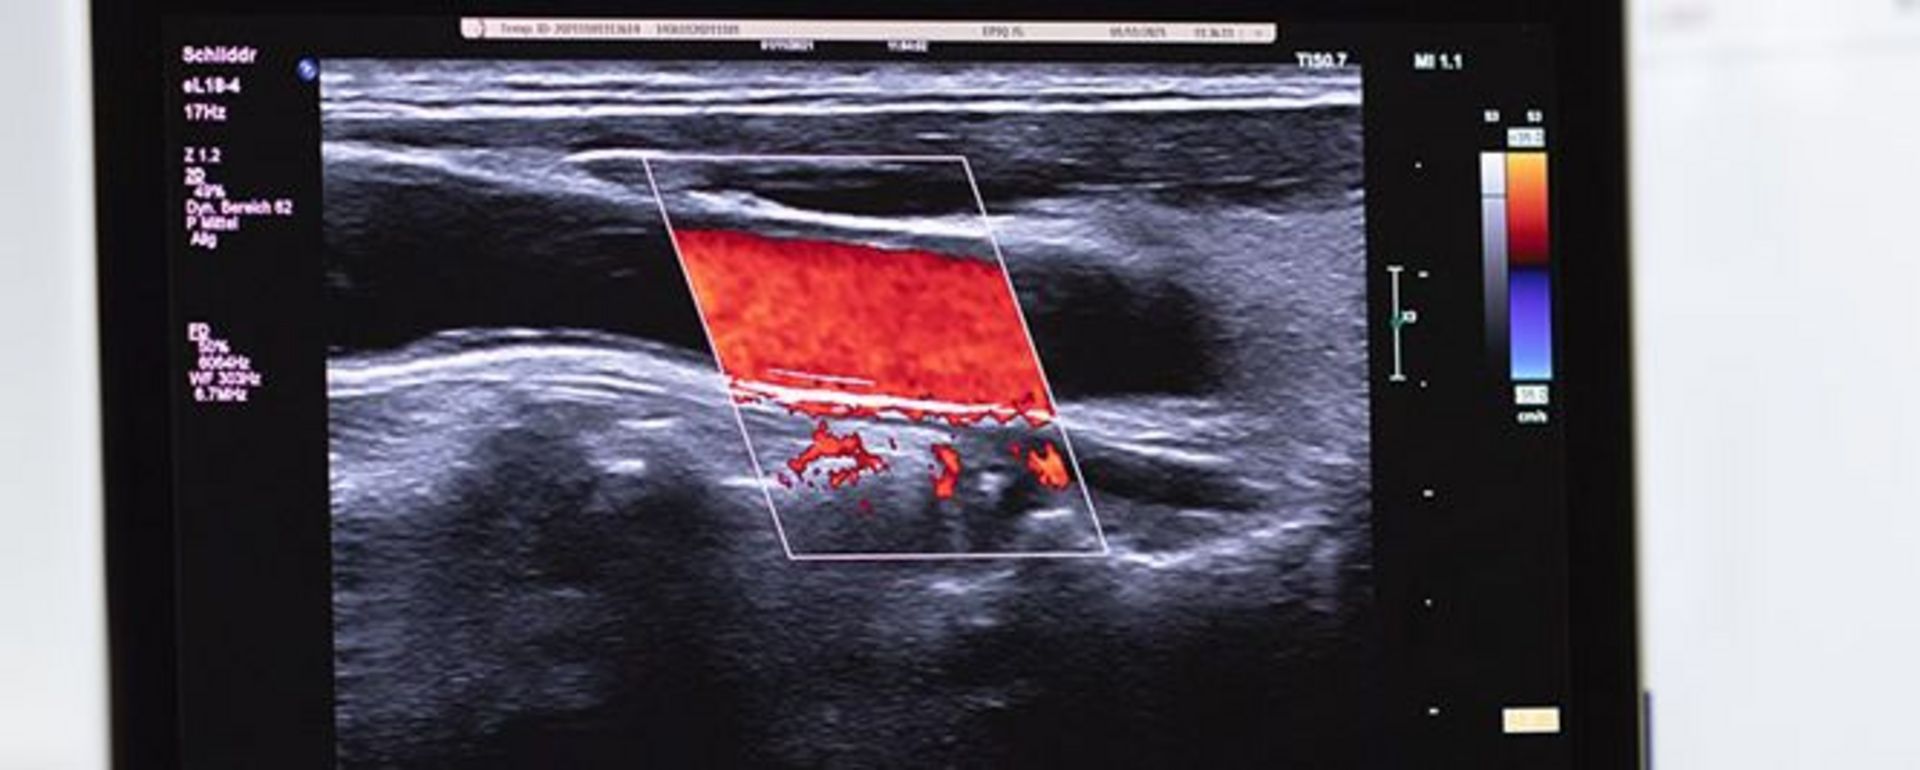

Medizintechnik

In der Medizintechnik werden Erkenntnisse und Methoden aus den Naturwissenschaften, den Ingenieurwissenschaften und der Medizin genutzt, um Verfahren und Systeme für die Diagnostik von Krankheiten, für deren Therapie und für die Rehabilitation zu entwickeln. Die Medizintechnik ist durch eine starke interdisziplinäre Zusammenarbeit verschiedener Fachgebiete geprägt. Dieser Umstand wirkt sich auch auf die Inhalte des Studienschwerpunktes aus.